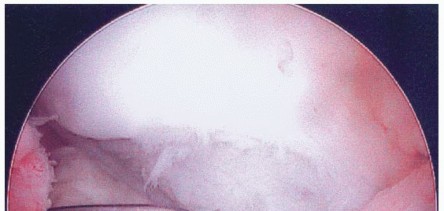

In OCD, operative treatment goals are to maintain joint congruity, rigidly fix unstable fragments, and repair osteochondral defects, thereby reducing symptoms and preventing additional cartilage deterioration (

FIG 7

).

Unstable lesions have fibrous tissue and a sclerotic bony rim behind them that is best removed to allow healing to occur (

FIG 8

). Furthermore, any joint fluid beneath a

fragment will prevent formation of a fibrin clot, thereby preventing the first step necessary for bony healing.

FIG 8 • Arthroscopic image of medial femoral condyle OCD lesion. The probe is used to hinge the lesion open, demonstrating fibrous tissue beneath lesion.